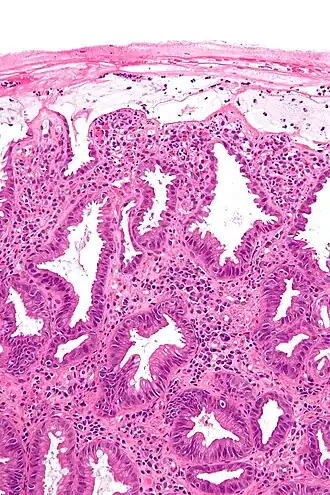

![]() Microfotografía de la mucosa del colon en un caso de colitis isquémica. | ||

La colitis isquémica es una enfermedad del aparato digestivo que afecta al colon y se produce porque esa porción del intestino recibe de forma transitoria un aporte de sangre insuficiente (isquemia). Se manifiesta con gravedad variable, dependiendo del calibre del vaso sanguíneo afectado, en las formas más graves provoca necrosis del colon con perforación del órgano y peritonitis secundaria que puede ser mortal, sin embargo a veces ocasiona molestias tan leves que el paciente no llega siquiera a consultar con el médico. Se estima que se producen entre 4,5 y 44 casos por 100 000 habitantes y año, siendo más frecuente en mayores de 65 años.[1]